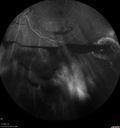

50 year old man: The patient noticed a few days ago, when putting on Contact Lenses for work which were slightly different from his usual strength. He therefore had some trouble at work with the new contact lenses. Then he had some haze in his vision. In the morning he went to see his mother in Venice and there was a new big black line in the left eye when he was getting up from lying down (this was yesterday). Then he noticed a lot of floaters in his vision that looked like blood. This has been fluctuating. You saw him this morning and asked him to come here. VA OD: Dcc20/20-2 NscJ1+ The patient has type I diabetes diagnosed at age 24 and he is now 50 years old VA OS: Dcc20/25+2 NscJ1+ IOP: TP: OD:17 OS:19

PDR and Vitreous Hemorrhage - High Risk Left Eye - Low Risk Right Eye412 views50 year old man with type I diabetes mellitus for 26 years. New Vitreous Hemorrhage in the left eye. Both eyes have NVE. Both also have foveal hypoplasia00000